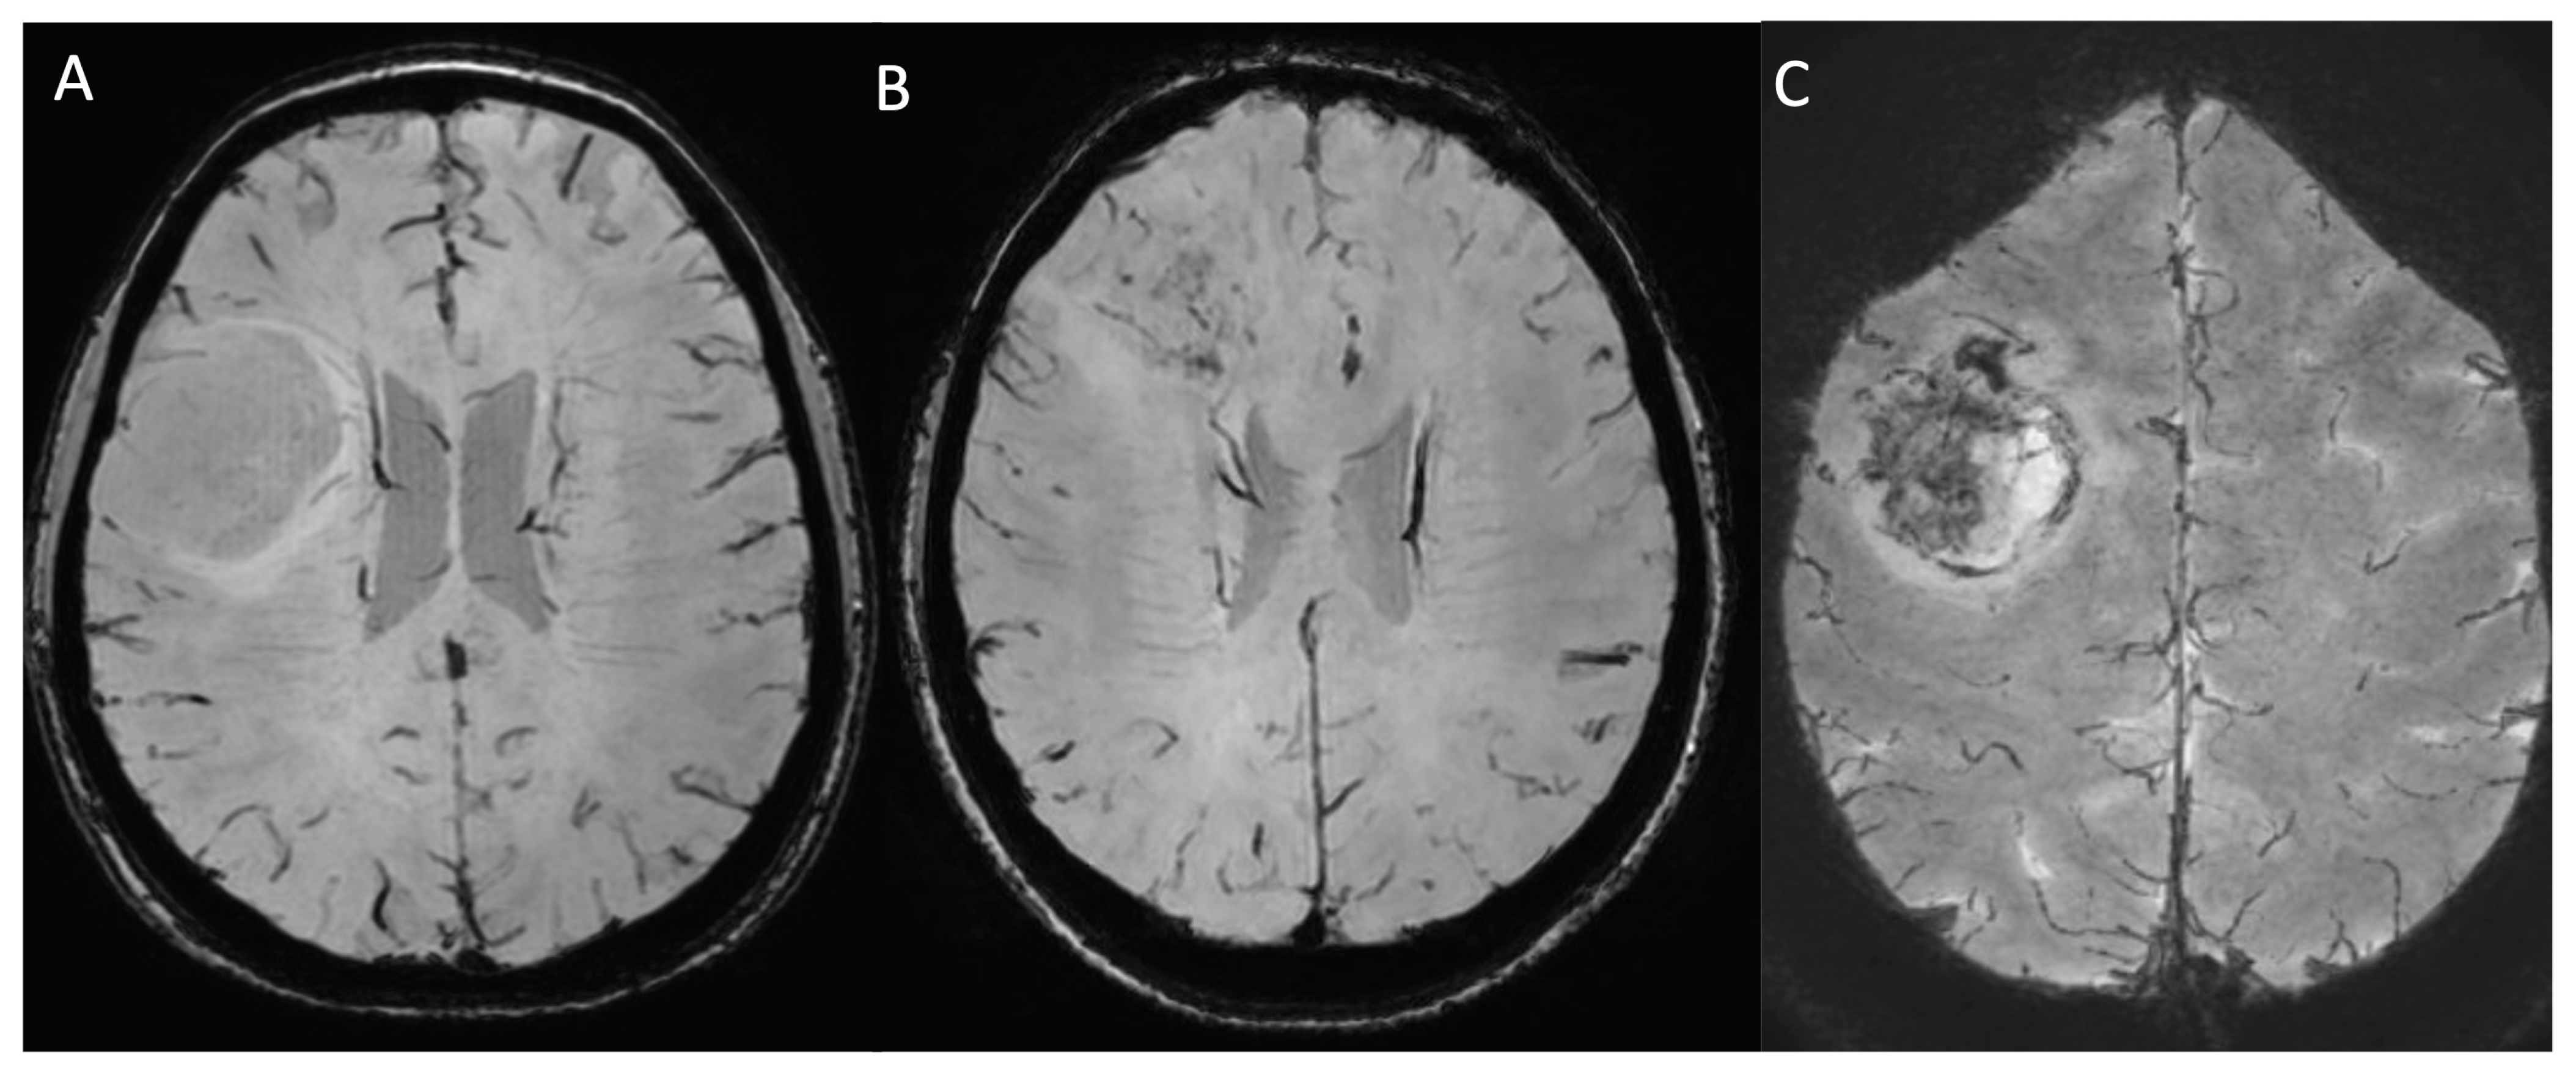

2.2.4. Susceptibility-Weighted Imaging

2.2.5. Diffusion-Weighted Imaging and Apparent Diffusion Coefficient Map